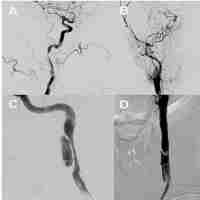

| Abstract | Background Cervicocerebral artery dissection is an important cause of ischemic stroke in young and middle-aged individuals. However, very few studies have compared the differential features between internal carotid artery dissection (ICAD) and vertebral artery dissection (VAD), including both cervical and intracranial artery dissections. We conducted a study to investigate the predisposing factors and radiological features in patients with ICAD or VAD. Methods All cases diagnosed with cervicocerebral artery dissection, ICAD, or VAD were identified through a medical records database, between January 2010 and January 2020. Baseline characteristics, predisposing factors, and radiological features of ICAD versus VAD were compared. Results A total of 140 patients with cervicocerebral artery dissection were included in the study, including 84 patients in the ICAD group and 56 in the VAD group. The mean age of patients in the ICAD and VAD groups was 43.37 ± 14.01 and 41.00 ± 12.98 years old, respectively. Patients with ICAD were more likely to be men compared with VAD (85.71% vs. 67.86%, p = 0.012). The frequency of hypertension, diabetes, smoking, drinking, and cervical trauma did not differ between ICAD and VAD. Dissections of ICAD were more frequently at the extracranial portions of the artery compared with those of VAD (70.24% vs. 44.64%, p = 0.003). In contrast, dissections of VAD were more common in the intracranial artery (55.36% vs. 29.76%, p = 0.003). Radiologically, double lumen (36.90% vs. 19.64%, p = 0.029) and intimal flap (11.90% vs. 1.79%, p = 0.029) were more frequently observed in ICAD than in VAD, and dissecting aneurysms were less frequent (13.10% vs. 26.79%, p = 0.041). Conclusions The distributions of cervical and intracranial artery dissections were different between ICAD and VAD. The frequencies of radiological features detected in patients with ICAD and VAD also differed. |